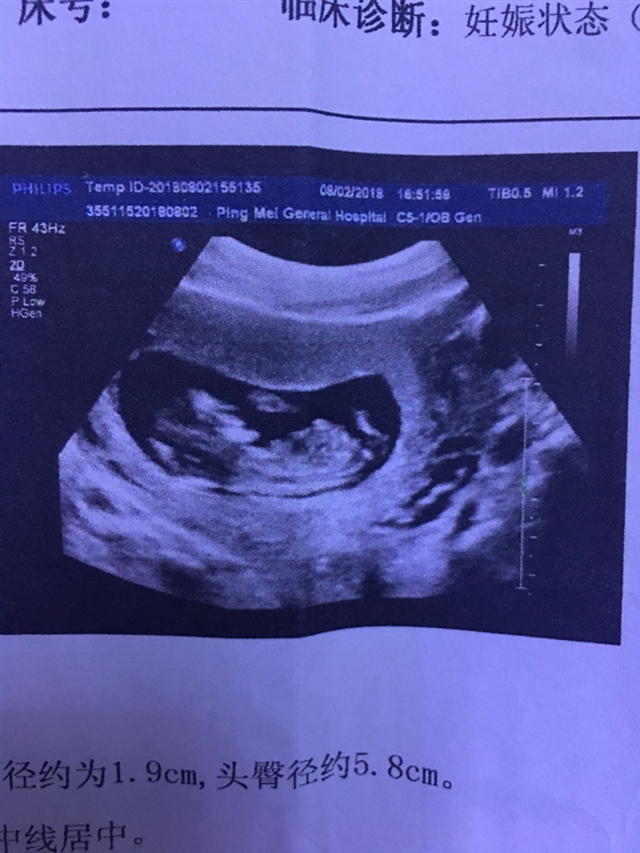

孕8周+2天